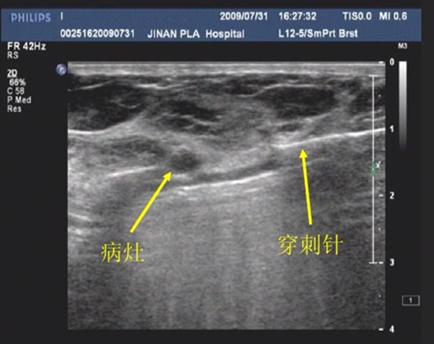

乳腺纤维腺瘤手术主要为传统开口手术和微创手术两种。对于微小的纤维腺瘤适宜选择微创旋切治疗;距乳晕较近的可选择环乳晕切口;较大的纤维腺瘤宜选择乳房下皱襞切口。传统的开口手术一般选择乳晕切口,因为女性乳晕皮肤薄富有弹性、易于伸展,切口在乳晕边缘,正好是皮肤色差的部位,受到乳晕皮脂腺和乳晕皮肤色素的修饰,术后瘢痕不十分明显。而且乳晕处血供丰富,利于切口愈合。环乳晕切口适用于肿瘤直径较小且距乳晕外缘较近的患者。经过美容缝合,恢复好的患者瘢痕一般比划隐蔽。微创手术的优点也相当明显,其手术切口只有3毫米大小,约为大米粒大小。手术中,手术医师通过彩超的引导,可以直接定点清除肿块,手术时间短,恢复快,但是其手术费用较高。一般来说为了防止残留,微创手术建议3公分以下的患者选择。